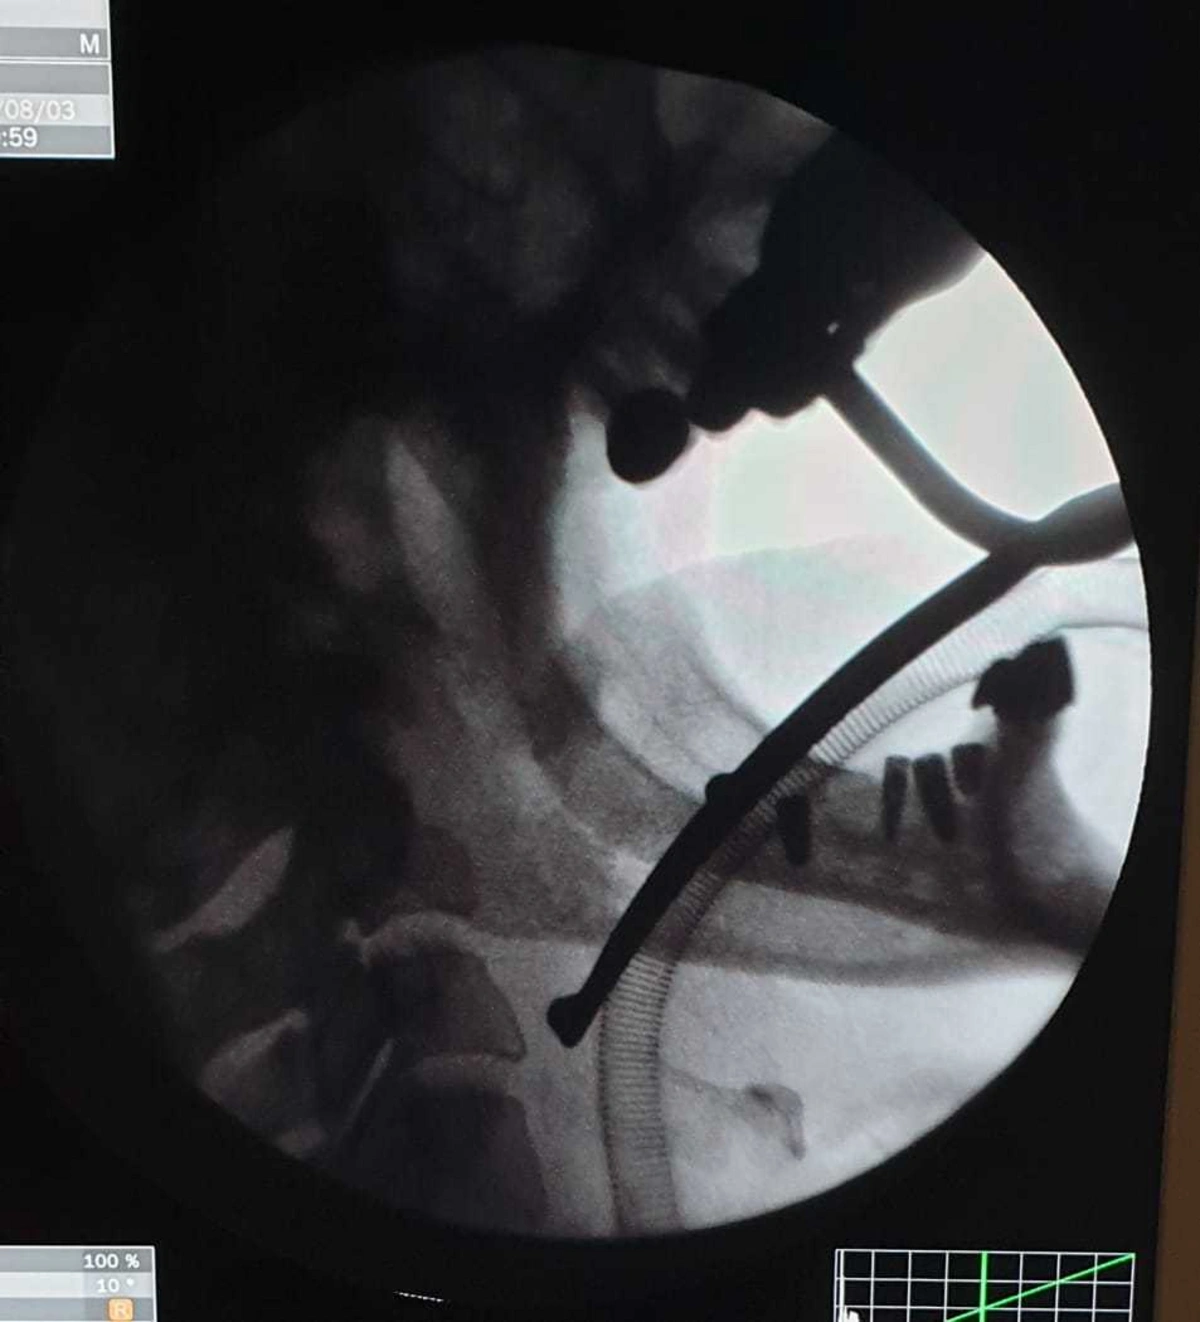

Как сообщает Report, хирург удалил фрагмент иглы длиной около 2 см, оставшийся в горле пациентки во время операции по удалению небной миндалины (тонзиллэктомия), проведенной десять лет назад.

По словам Э.Акбарова, тонзиллэктомия сама по себе непростая операция: "Но в большинстве случаях операцию проводят под местным наркозом и в несоответствующих амбулаторных условиях. Эта операция требует специальных навыков. Во время тонзиллэктомии в 2009 году у пациентки началось кровотечение из правого миндаликового ложа. Для остановки кровотечения было принято решение наложить швы на рану. Во время этой процедуры игла сломалась и сломанный фрагмент остался в мягких тканях шеи. Операция длится четыре часа, кровотечение останавливается, но сломанную иглу обнаружить не удается. В послеоперационный период у пациентки отмечались боли в правом отделе шеи, особенно при глотании и наклоне шеи. Но в то время в ходе радиологического обследования медицинскому персоналу не удалось выявить проблему, а пациентке сказали, что проблема является субъективной".

Хирург-оториноларинголог отметил, что инородное тело было обнаружено случайно: "Во время стоматологического осмотра с проведением компьютерной томографии в горле пациентки был обнаружен фрагмент хирургической иглы. Таким образом, предположения, что жалобы пациентки возникали из-за оставшегося фрагмента хирургической иглы, подтвердились. Несмотря на многочисленные обращения, многие специалисты заявляли о рискованности операции и отказывались ее выполнять. Повторная компьютерная томография, проведенная обратившейся к нам пациентке, подтвердила, что инородное тело находилось в опасной зоне. Путем трансоральной фаринготомии с доступом через горло инородное тело было извлечено. Во время операции и послеоперационный период каких-либо осложнений не было. Пациентка находилась под наблюдением врачей до полного выздоровления".